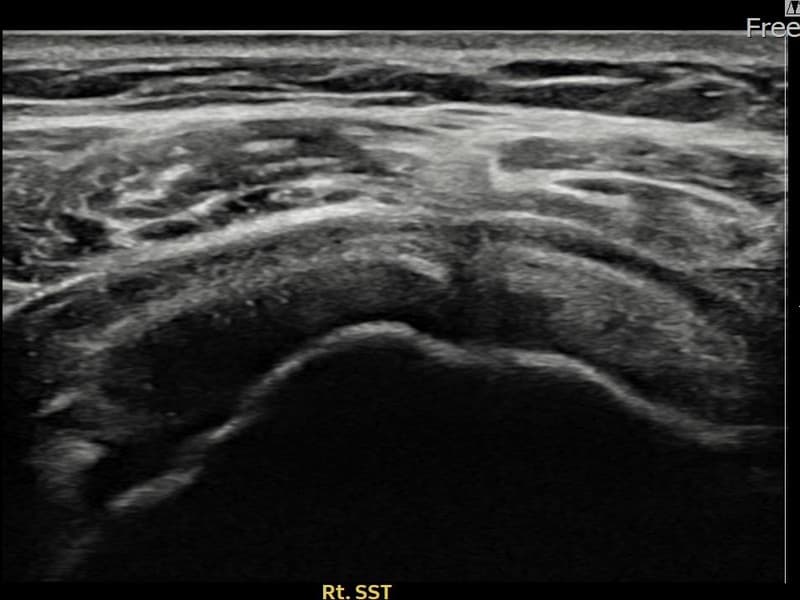

시술 전 초음파 측정 결과 파열 크기는 7mm × 3mm (힘줄 두께의 약 30% 결손)로 확인되었습니다. 시술 전 초음파에서 우측 극상근건 관절면측의 에코 단절과 힘줄 결손 소견이 확인되었습니다. 시술 후 초음파에서 파열 부위에 재생 조직이 형성되고 힘줄 연속성이 회복된 것이 관찰되었습니다.

60대 초반 여성 환자분으로, 집안일과 텃밭 작업을 꾸준히 하시다가 우측 어깨 통증이 서서히 심해져 내원하셨습니다. 팔을 60~120도 구간에서 들어 올릴 때 충돌 통증이 심하고, 야간에도 어깨를 짓누르는 듯한 통증이 있어 수면에 지장이 있으셨습니다. 초음파 검사에서 우측 극상근건 관절면측 부분파열이 확인되었으며, 힘줄 내 에코 단절이 뚜렷한 상태였습니다. 수술 없이 초음파 유도 하 축소봉합술을 시행하였고, 당일 귀가 후 재활 운동을 단계적으로 진행하셨습니다. 시술 11주 후 추적 초음파에서 파열 부위 연속성이 회복되고 충돌 증상이 소실되어 정상 생활에 복귀하셨습니다.